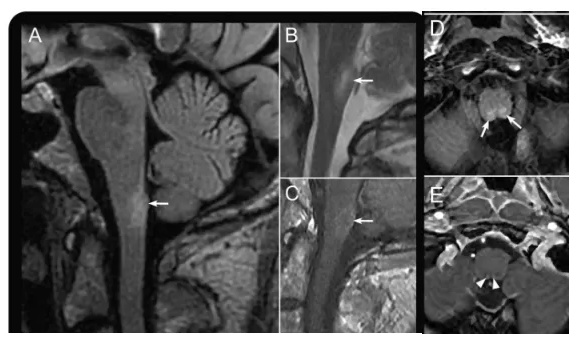

NMOSD患者MRI检查显示延髓极后区病变(箭头所示)